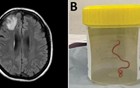

女子大脑有蛔虫